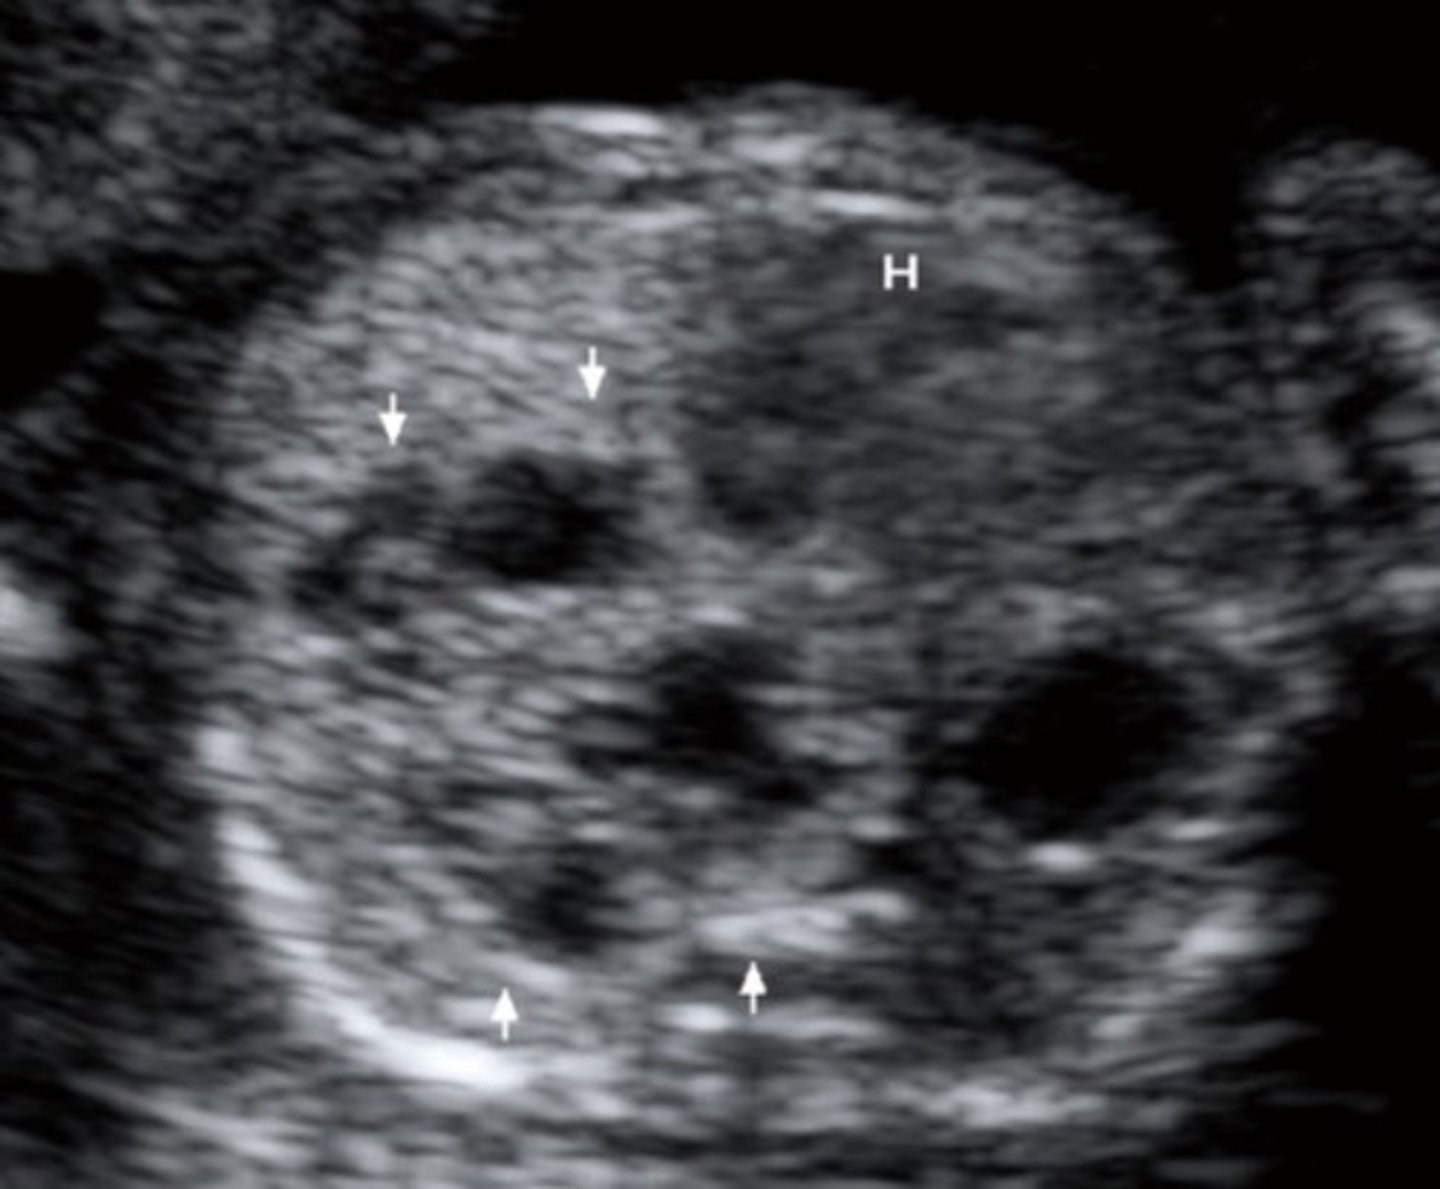

Choroid Plexus Cysts

Must be at least 2mm

Associated with Trisomy 18